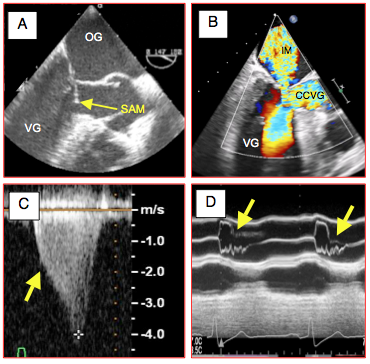

A cause de la subobstruction provoquée par le SAM, la Vmax dans la CCVG dépasse 2.5 m/s [7,14]. Le flux baisse dans l’aorte et la réouverture de la mitrale en cours de systole induit une insuffisance méso-télésystolique. Ce phénomène est bien visible en 4 cavités ou en long axe du VG mi-oesophage (Vidéo). La chute du débit systolique en cours de systole ne permet plus à la valve aortique de rester ouverte. En mode TM de la valve aortique (40° ou 120°), on voit collaber les cuspides en cours de systole ; cette image est très pathognomonique. La vélocité du flux aortique augmente très rapidement en cours d’éjection et l’image spectrale prend une forme en dague (Figure 27.6) [9].

Figure 27.6 : Obstruction dynamique de la chambre de chasse du VG (CCVG). A: coudure du feuillet mitral antérieur qui bascule dans la CCVG en cours de systole (SAM: systolic anterior motion) en vue long-axe 140°. B: au Doppler couleur, présence d'une insuffisance mitrale (IM) et d'un flux tourbillonnaire systolique dans la CCVG (Vmax > 2.5 m/s); on voit une zone d'accélération à l'entrée de la CCVG. C: aspect "en dague" du flux aortique au Doppler spectral, dû à la chute du volume systolique (courbe rétrécie) et à l'accélération du flux (subobstruction de la CCVG); le décrochage (flèche) est synchrone de la survenue su SAM. La Vmax est ici de 4 m/s. D: collapsus mésosystolique des cuspides aortiques en mode TM par effondrement du volume systolique dès que s'installe le SAM.

A cause de la subobstruction provoquée par le SAM, la Vmax dans la CCVG dépasse 2.5 m/s [7,14]. Le flux baisse dans l’aorte et la réouverture de la mitrale en cours de systole induit une insuffisance méso-télésystolique. Ce phénomène est bien visible en 4 cavités ou en long axe du VG mi-oesophage (Vidéo). La chute du débit systolique en cours de systole ne permet plus à la valve aortique de rester ouverte. En mode TM de la valve aortique (40° ou 120°), on voit collaber les cuspides en cours de systole ; cette image est très pathognomonique. La vélocité du flux aortique augmente très rapidement en cours d’éjection et l’image spectrale prend une forme en dague (Figure 27.6) [9].

Figure 27.6 : Obstruction dynamique de la chambre de chasse du VG (CCVG). A: coudure du feuillet mitral antérieur qui bascule dans la CCVG en cours de systole (SAM: systolic anterior motion) en vue long-axe 140°. B: au Doppler couleur, présence d'une insuffisance mitrale (IM) et d'un flux tourbillonnaire systolique dans la CCVG (Vmax > 2.5 m/s); on voit une zone d'accélération à l'entrée de la CCVG. C: aspect "en dague" du flux aortique au Doppler spectral, dû à la chute du volume systolique (courbe rétrécie) et à l'accélération du flux (subobstruction de la CCVG); le décrochage (flèche) est synchrone de la survenue su SAM. La Vmax est ici de 4 m/s. D: collapsus mésosystolique des cuspides aortiques en mode TM par effondrement du volume systolique dès que s'installe le SAM.